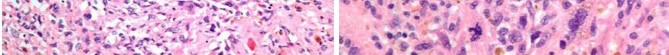

A 15-year-old male presents with deep knee pain awakening him at night. Radiographs show a permeative destructive lesion in the distal femoral metaphysis with a 'sunburst' periosteal reaction and Codman's triangle.

Biopsy confirms high-grade conventional osteosarcoma. What is the most critical prognostic factor for long-term overall survival in this patient?

Explanation

For localized high-grade osteosarcoma, the most important prognostic indicator is the histologic response to neoadjuvant chemotherapy. This is evaluated during the definitive resection. A 'good response' is typically defined as greater than 90% or 99% tumor necrosis. Patients who achieve this level of necrosis have a significantly improved disease-free and overall survival rate compared to 'poor responders' who have extensive viable tumor cells remaining.